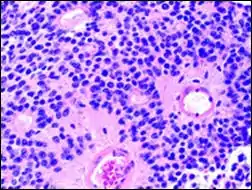

Perivascular pseudorosette

A perivascular pseudorosette consists of a spoke-wheel arrangement of cells with tapered cellular processes radiates around a wall of a centrally placed vessel. The modifier “pseudo” differentiates this pattern from the Homer Wright and Flexner-Wintersteiner rosettes, perhaps because the central structure is not actually formed by the tumor itself, but instead represents a native, non-neoplastic element. Also, some early investigators argued about the definition of a central lumen, choosing “pseudo” to indicate that the hub was not a true lumen but contained structures. Nevertheless, this pattern remains extremely diagnostically useful and the modifier unnecessarily leads to confusion. Perivascular pseudorosettes are encountered in most ependymomas regardless of grade or variant. As such, they are significantly more sensitive for the diagnosis of ependymomas than true ependymal rosettes. Unfortunately, perivascular pseudorosettes are also less specific in that they are also encountered in medulloblastomas, PNETs, central neurocytomas, and less often in glioblastomas, and a rare pediatric tumor, monomorphous pilomyxoid astrocytomas.[2]

Micrograph of perivascular pseudorosettes

Structure of a perivascular pseudorosette